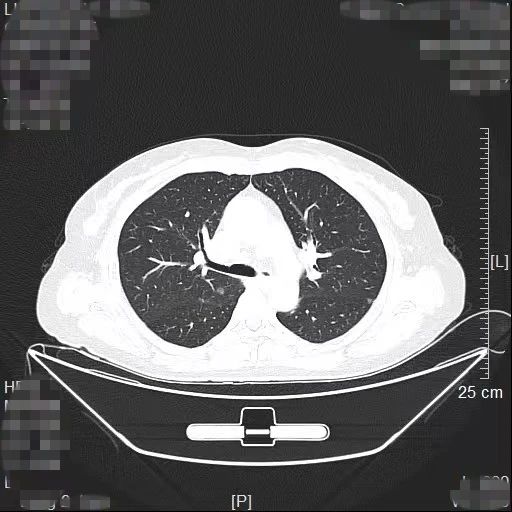

近日,我院胸部肿瘤外科方卫民主任医师团队通过“针孔消融+单孔微创”的杂交手术,为患者同时解除2个高危肺结节,手术切口仅为一个针眼加一个3cm的微创切口。